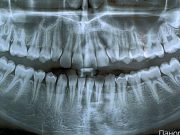

ИИ – самый лучший рентгенолог?

Компания Overjet, основанная выпускниками Массачусетского технологического института (MIT), разработала искусственный интеллект, который анализирует и комментирует рентгеновские снимки зубов. Цель компании — сделать работу стоматологов...